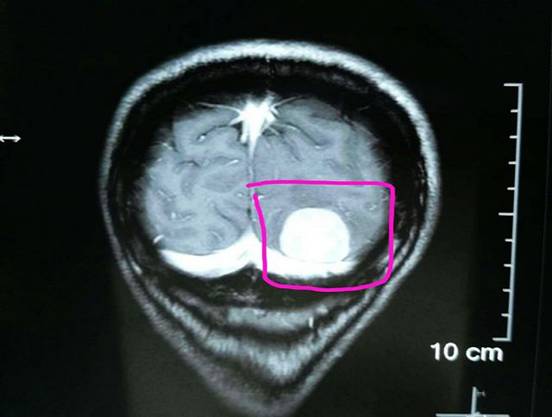

我院成功为一左侧天幕脑膜瘤患者实施肿瘤分块切除术 来自七病区神经外科消息:近日,一位来自唐家坊女性刘某患者,因半月前头痛、头昏、双眼畏光、视疲劳入住我院神经外科,经核磁共振检查示左侧枕部占位病变,脑膜瘤?后完善术前检查,于11月4日手术,在显微镜下成功实施了肿瘤分块切除一3*2cm大小肿块,术后患者无任何神经症状,恢复良好,头部复查CT显示,原肿瘤组织消失,患者生命体征正常,无头痛,头晕现象。 术后,患者家属为能如此迅速而完美的成功手术而感到欣慰满意! (撰稿 菊荣) 据悉,在显微镜下成功实施脑膜瘤切除术为我县历史上首例,这也成功标志着我院神经外科手术水平又上了一个新的台阶。 图为 手术中。 图为 在显微镜下手术中。 图为 患者术前核磁共振影像资料,右侧红色标识处为枕部脑膜瘤。 图为 术中切除的肿块 (编辑 铭培) |